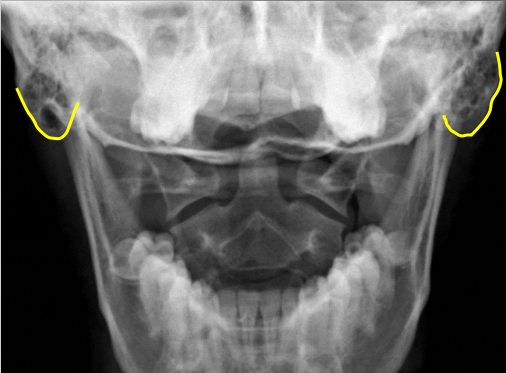

yellow

Occipital condyles

blue

Foramen magnum